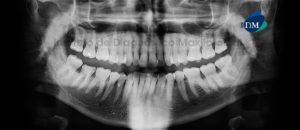

Paciente masculino de 16 años de edad es referido al Instituto de Diagnóstico Maxilofacial (IDM) para su evaluación y diagnóstico. A la evaluación de la